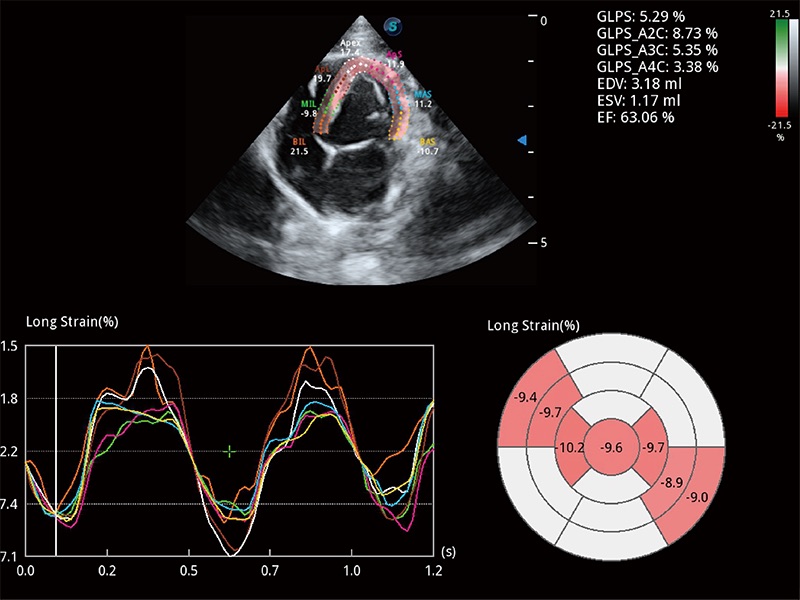

通过心肌识别技术与二维斑点追踪技术相结合,对心脏的超声图像进行量化分析。计算心肌17个节段的应变、应变率、速度、位移等,并通过牛眼图的形式进行呈现。

具备多种协议可选,同时支持17阶段划分法和专业的SE报告。